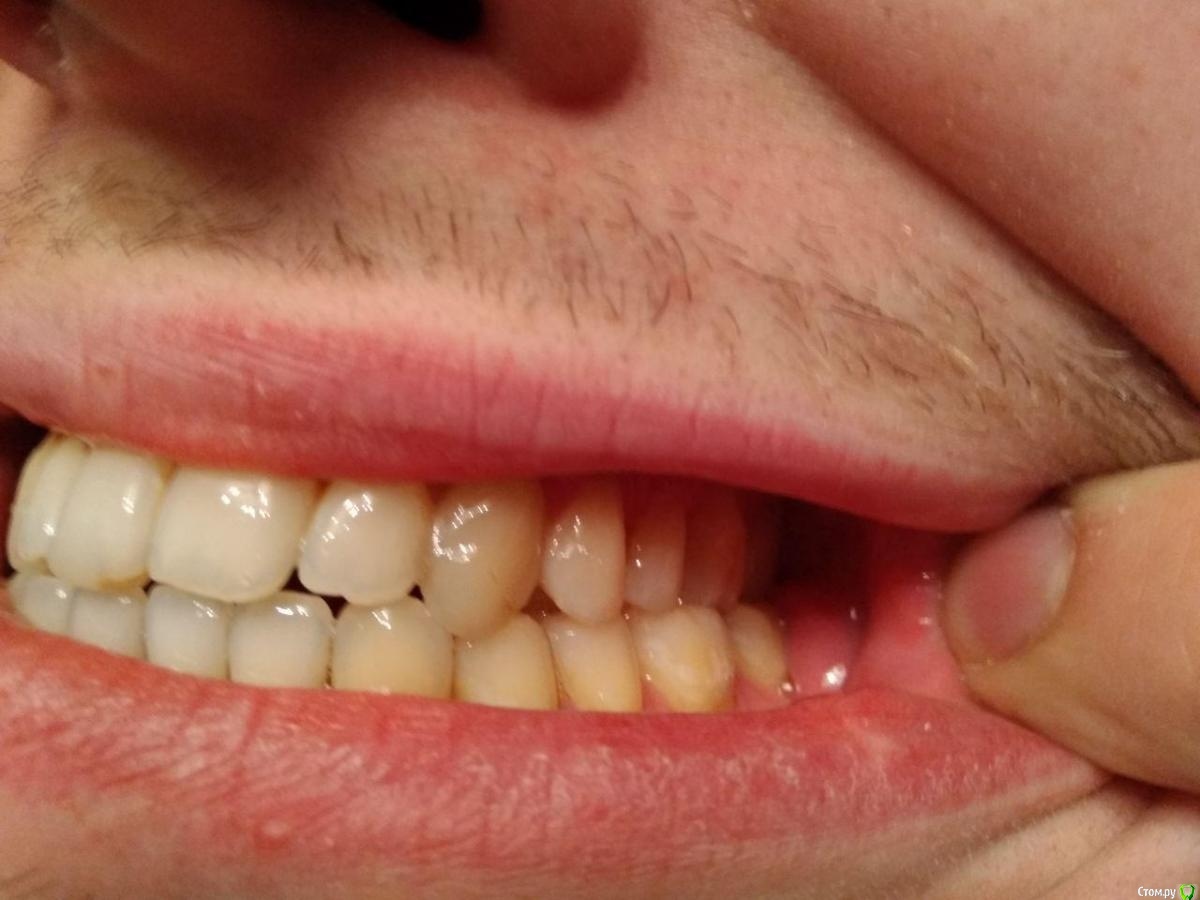

Здравствуйте, мне 29 лет, хочу остаться со своими зубами и не угробить ВНЧС.

С 16-20 лет проходил лечение у ортодонта (2 года расширитель на верхней челюсти, 2 года брекеты). Итог - получили, так называемый камуфляж (как я сейчас понимаю).

В данный момент ситуация усугубилась, основные проблемы - множественные рецессии и хруст в ухе при глотании.

2ой Провел диагностику, ТЭНС терапию, сделал капу на нижнюю челюсть (хруст при зевании прекратился, при глотании все равно слышно), про  рецессию было сказано, что некоторые зубы получают неправильную нагрузку, но причина именно множественной рецессии не в прикусе. Дальнейшие предложении - устранение перекрестного прикуса с помощью брекетов или оклюзионного протокола.